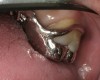

Initial examination revealed a partial edentulous patient with extensive wear of the maxillary anterior teeth and moderate wear in the mandibular teeth (Figure 1, Figure 2, Figure 3 , Figure 4, Figure 5, Figure 6 and Figure 7). The patient's maxillary and mandibular RPDs also showed excessive wear and multiple signs of fractures (Figure 2 and Figure 3). The patient had been wearing a mandibular nightguard for 8 years.

Figure 4  Intraoral occlusal view of maxillary dentition presenting excessive signs of wear.

Figure 4